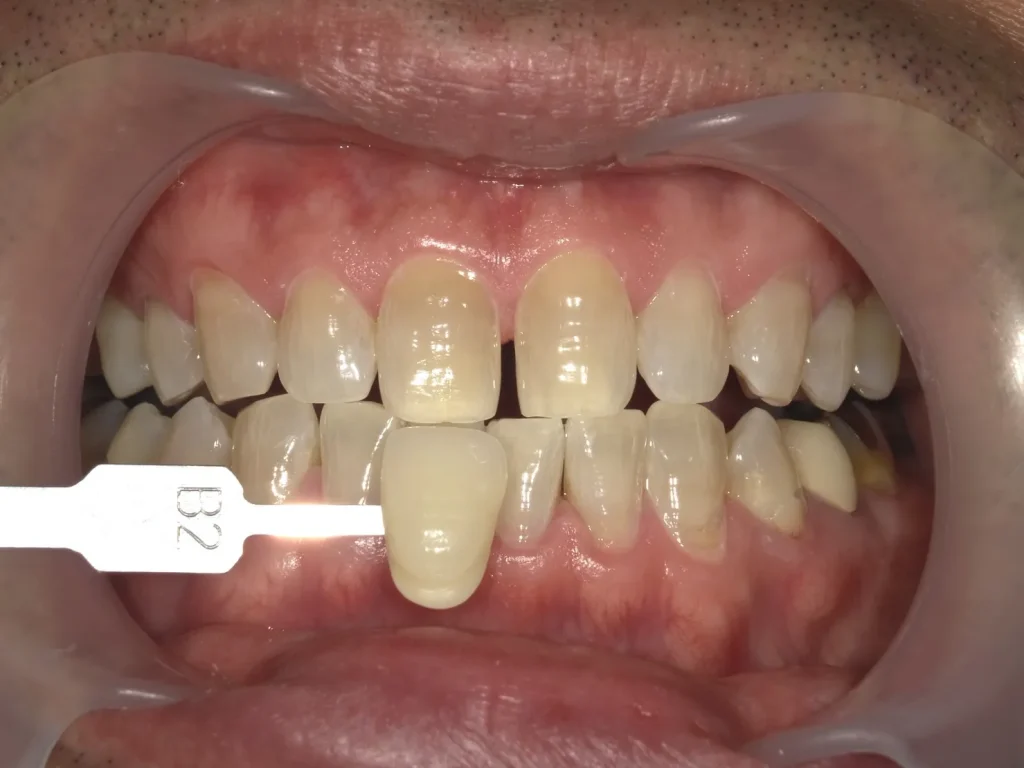

術前術後写真

歯科衛生士からのコメント

仕事の帰りが遅く、最初は一日30分くらいずつのホームホワイトニングでしたが、どんどん白くなるのが楽しくなり、途中から1.5時間くらいはがんばりました。

ホームホワイトニングの時間を延ばした直後から、少し違和感とシミを感じたそうですが、気になる程でもなかったとのことなので、そのまま継続してしてもらいました。